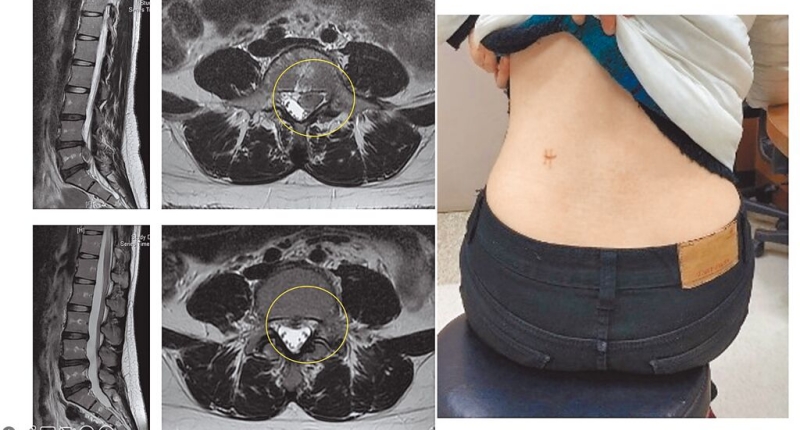

陳文鈐表示,內視鏡手術講究精準,透過術中透視X光機進行經皮穿刺定位,就像「點穴」,精準穿刺到達神經壓迫位置,利用環鋸進行椎間孔道擴張以利內視鏡進入,完成脊椎內視鏡工作通道後,就可進行骨除手術,傷口僅約0.6~1公分。

且內視鏡手術局部麻醉下就可以進行,病患全程清醒開刀,不需要全身麻醉,病人可以清醒與醫生對話,手術完回到病房就可以下床活動,且多數病患術後第二天就可出院。